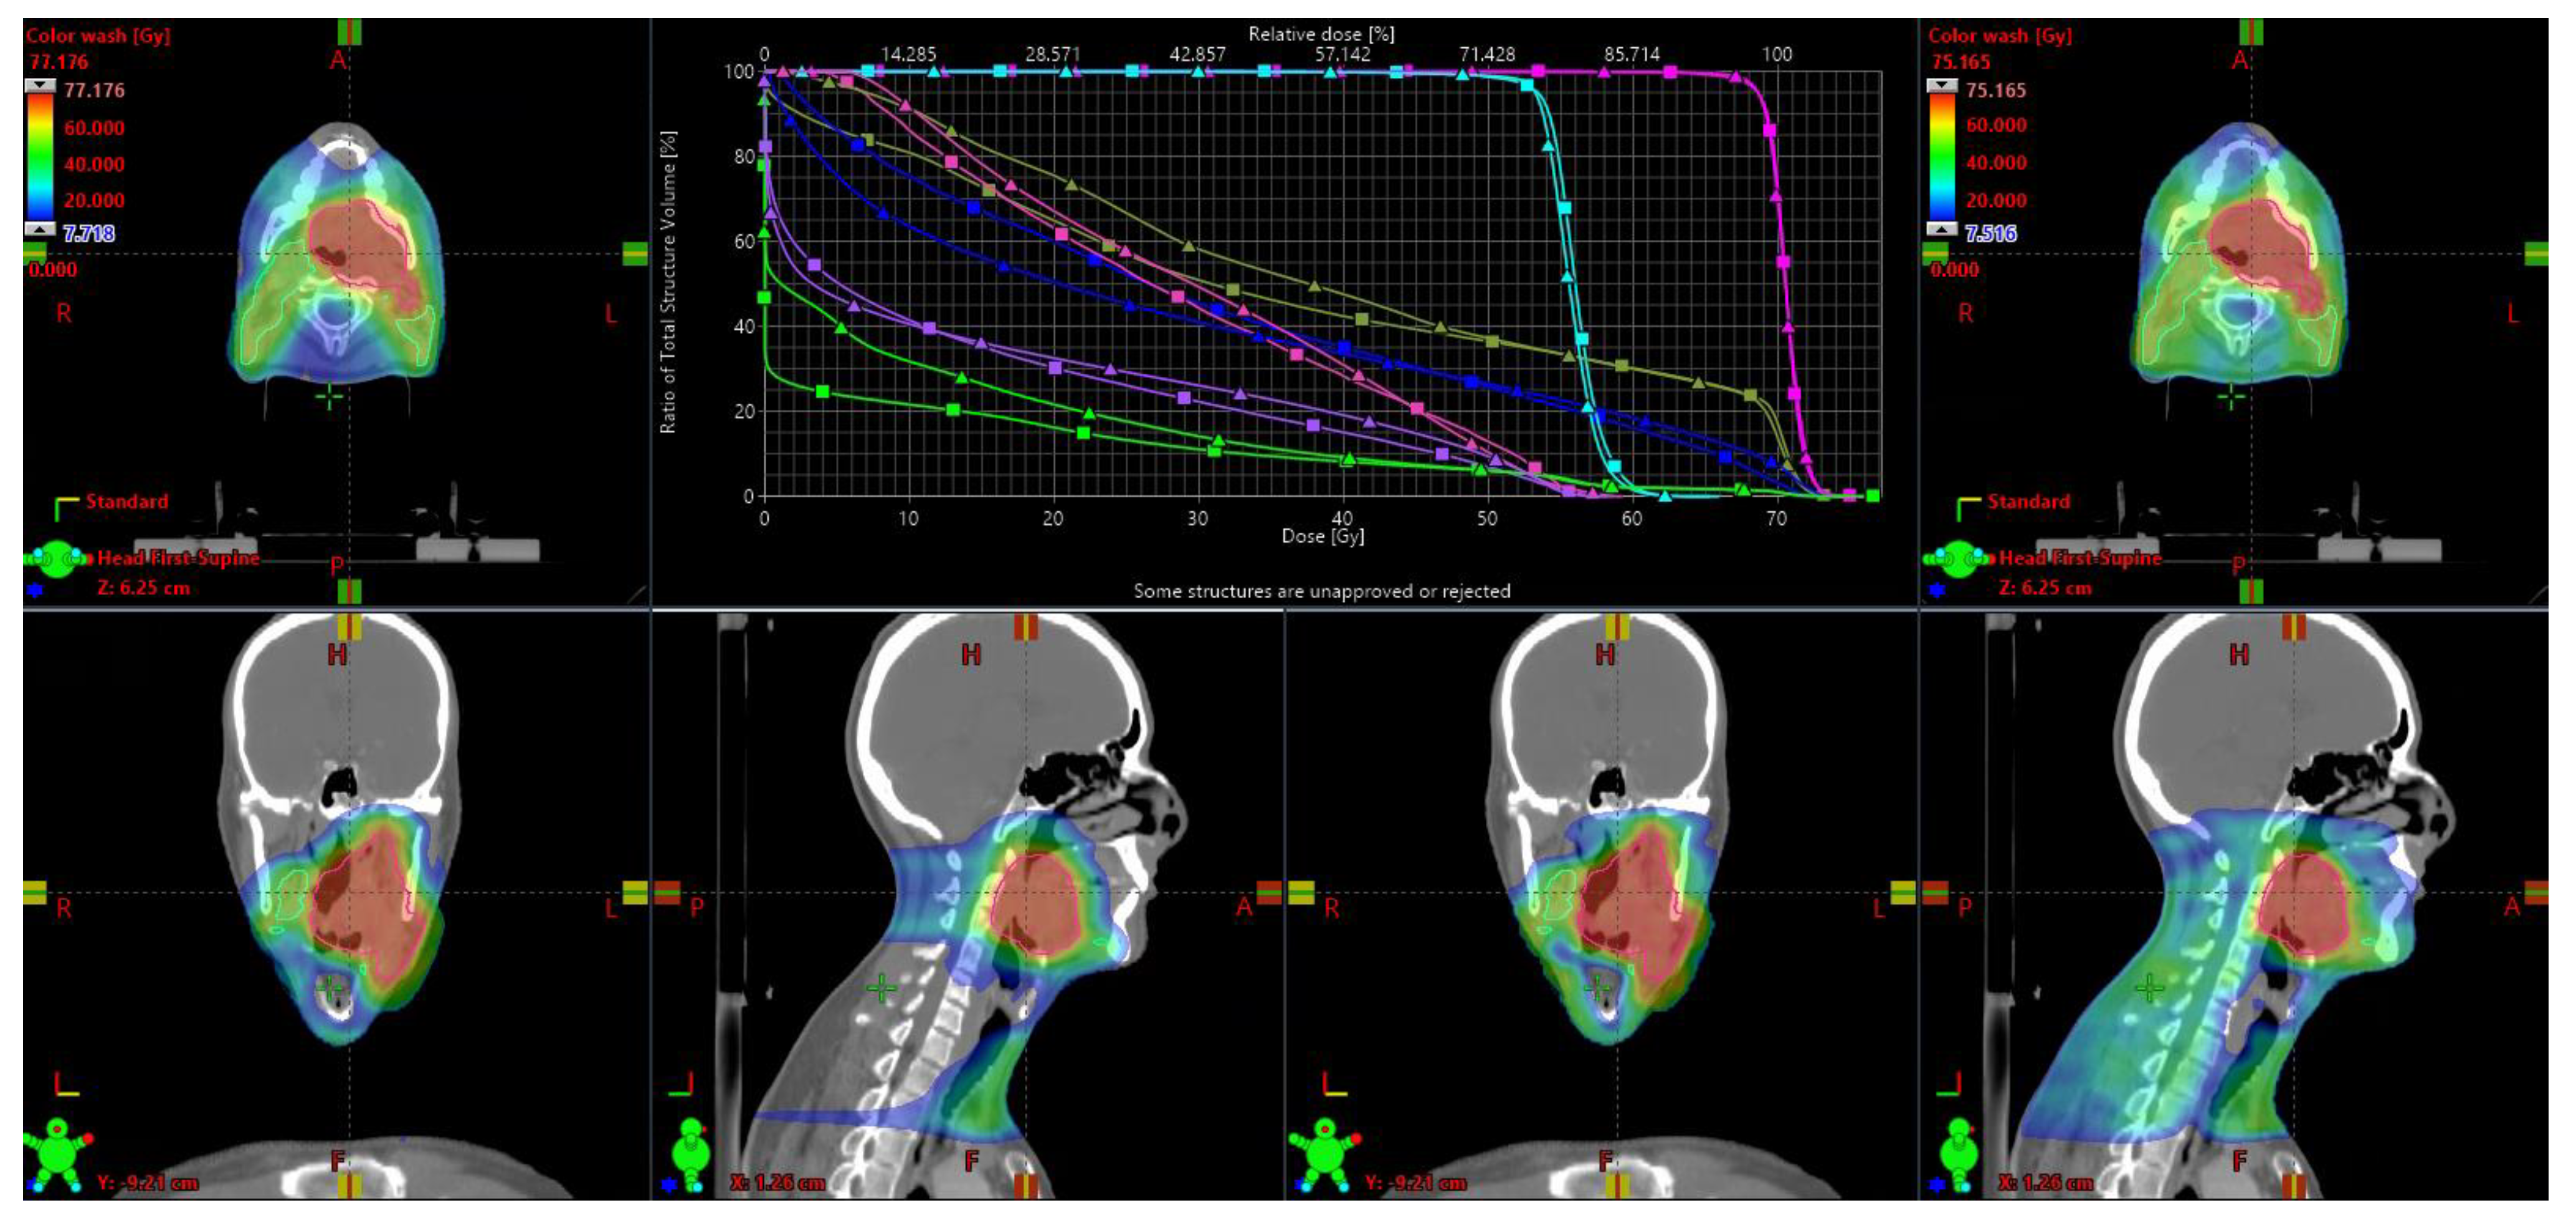

2.1. Treatment Planning and Quality Comparison

3.1. Quality Comparison

4.1. Plan Quality